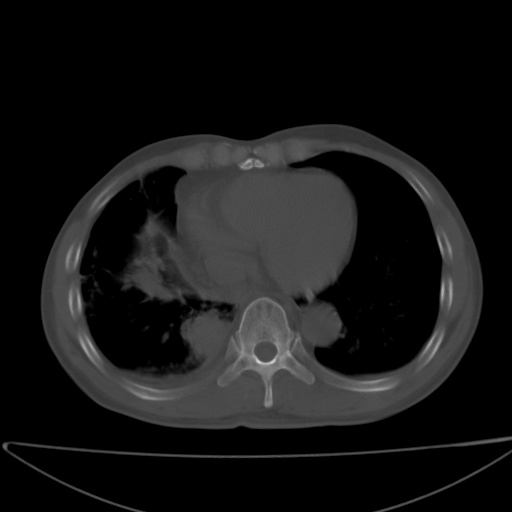

以下是引用jsgdoctor在2008-11-6 22:12:00的发言:[br]右主支气管壁明显增厚,管腔狭窄.考虑为右侧中央型肺癌伴阻塞性炎症\\肺脓肿.

以下是引用zjzjr在2008-11-6 20:25:00的发言:[br]中心型肺ca,合并阻塞性肺炎

以下是引用zsl6918在2008-11-6 19:43:00的发言:[br]右侧中心性肺癌(鳞癌)